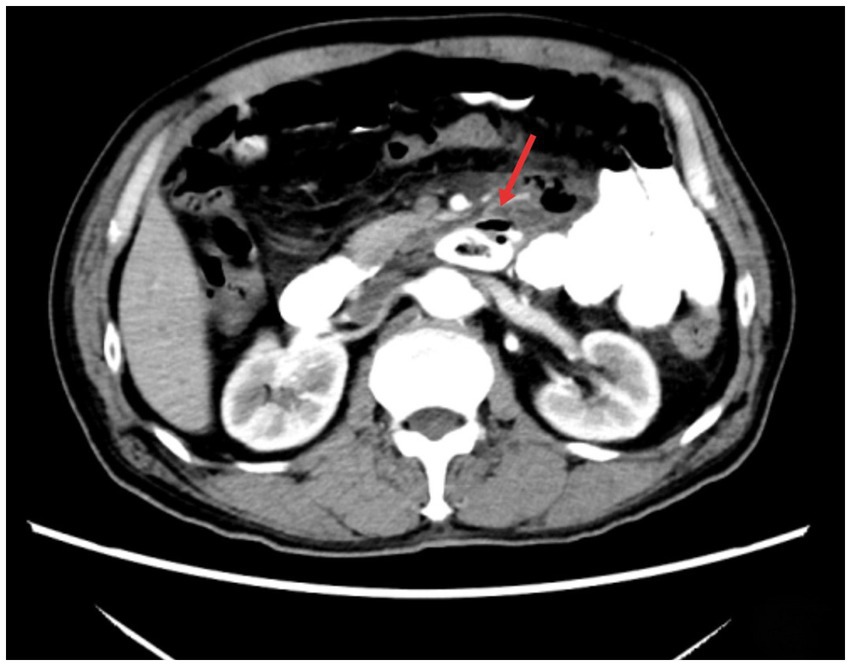

Figure 1

Abdominal CT shows a cystic shadow is seen in the third portion of the duodenum, with a hollow high-density area inside. A localized gas shadow is observed in front (indicated by the arrow).